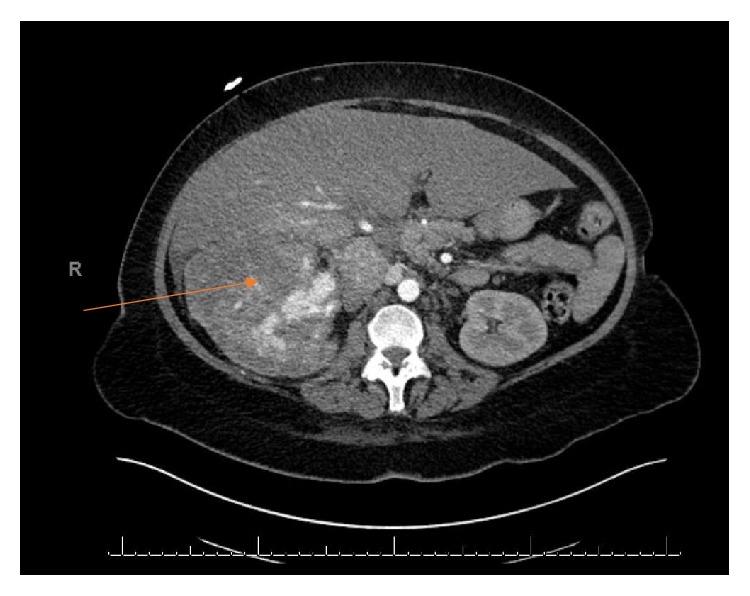

Renal cell carcinoma, particularly the most common clear cell type, is one of the most aggressive of urological cancers with significant risk of metastatic spread. It also has a propensity for venotropism with a proportion of tumors developing thrombi up to the right atrium. The response with newly adopted targeted therapy has been considered to be in the evolutionary stage with no clear role with respect to debulking or reducing the size of the inferior vena cava (IVC) thrombus. We describe a case of a right-sided metastatic RCC with Level IV thrombus initially managed with Pazopanib followed by Nivolumab and Adalimumab followed by cytoreductive nephrectomy and IVC thrombectomy in the post-targeted therapy setting with complete curative response.

肾细胞癌,尤其是最常见的透明细胞型,是侵袭性最强的泌尿系统癌症之一,具有显著的转移扩散风险。它还倾向于侵犯静脉,一部分肿瘤会形成血栓,甚至延伸至右心房。新采用的靶向治疗的疗效被认为尚处于发展阶段,对于减少下腔静脉(IVC)血栓的体积或清除血栓尚无明确作用。我们描述了一例右侧转移性肾细胞癌伴IV级血栓的病例,该病例最初采用帕唑帕尼治疗,随后使用纳武单抗和阿达木单抗,在靶向治疗后进行了减瘤性肾切除术和IVC血栓切除术,获得了完全治愈的效果。